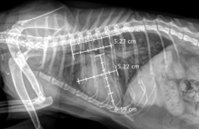

Fig. 2. Vertebral Heart Score (VHS) Measurement in a Cat with Congestive Heart Failure, Showing a VHS of 12

Table 7 shows that VHS increased progressively with disease stage, with mean values of 8.06 ± 0.15 in stage B1, 8.43 ± 0.32 in stage B2, and 9.83 ± 0.47 in stage C. This difference was highly statistically significant (p < 0.01), indicating a strong association between VHS and disease progression. Pathophysiologically, HCM is characterized by left ventricular myocardial hypertrophy accompanied by secondary left atrial enlargement. Although VHS does not directly reflect myocardial wall thickness, it allows assessment of overall cardiac silhouette size on thoracic radiographs. Therefore, VHS tends to increase more markedly in later stages, when left atrial enlargement plays a major role in altering cardiac silhouette morphology. In stage B1, VHS ranged from 7.80 to 8.20, close to the normal reference range in healthy cats. This is consistent with Sousa et al. (2025), who reported that thoracic radiography has low sensitivity for detecting early-stage HCM, because myocardial hypertrophy is not yet sufficient to cause obvious changes in cardiac silhouette. In stage B2, when hemodynamic alterations and cardiac remodeling become more evident, VHS increased slightly, in parallel with echocardiographic changes such as increased LA/Ao ratio and interventricular septal thickness. However, VHS may still not exceed clear diagnostic thresholds, highlighting its limitation in screening pre–heart failure HCM. In stage C, VHS increased markedly, with a mean of 9.83 and values up to 10.5 in some cases. This corresponds to the congestive heart failure stage, when severe left atrial enlargement, pulmonary edema, or pleural effusion markedly alter cardiac silhouette appearance. This finding is consistent with reports by Ironside et al. (2021), in which high VHS values are considered a typical radiographic sign of heart failure in cats with HCM.

Pathophysiologically, HCM is characterized by left ventricular myocardial hypertrophy accompanied by secondary left atrial enlargement and could explain the strong association between VHS and disease progression portrayed in Table 7. Although VHS does not directly reflect myocardial wall thickness, it allows assessment of overall cardiac silhouette size on thoracic radiographs. Therefore, VHS tends to increase more markedly in later stages, when left atrial enlargement plays a major role in altering cardiac silhouette morphology (Sousa et al., 2025). The observation in stage B1 where VHS ranged from 7.80 to 8.20 (Table 7), is close to the normal reference range in healthy cats, and consistent with Sousa et al. (2025), who reported that thoracic radiography has low sensitivity for detecting early-stage HCM, because myocardial hypertrophy is not yet sufficient to cause obvious changes in cardiac silhouette. In stage B2, when hemodynamic alterations and cardiac remodelling become more evident, VHS increased slightly, in parallel with echocardiographic changes such as increased LA/Ao ratio and interventricular septal thickness. However, VHS may still not exceed clear diagnostic thresholds, highlighting its limitation in screening pre–heart failure HCM. In stage C, VHS increased markedly, and corresponds to the congestive heart failure stage, when severe left atrial enlargement, pulmonary oedema, or pleural effusion markedly alter cardiac silhouette appearance. This finding is consistent with reports by Ironside et al. (2021), in which high VHS values are considered a typical radiographic sign of heart failure in cats with HCM. With regards to echocardiographic indices, there was a significantly marked increase in LA/Ao ratio (Figure 3), reflective of the pathophysiology of HCM: left ventricular hypertrophy → reduced compliance → increased filling pressure → progressive left atrial enlargement over time. The LA/Ao value in stage C exceeded the reference threshold in the ACVIM Consensus Statement (2020), indicating chronically elevated filling pressures and high risk of pulmonary oedema and heart failure. This is consistent with Fuentes et al. (2020), who identified LA/Ao as the strongest predictor of congestive heart failure in HCM.